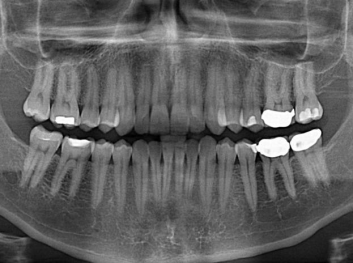

Adam Celiz,是來自諾丁漢大學(xué)的研究人員,他和同事開發(fā)的這種新型合成生物材料,能刺激干細胞在牙髓部的生長。與普通材料一樣,這種合成材料被填充到牙齒并用UV光硬化。

在體外測試中,材料刺激干細胞進入牙本質(zhì)的增殖和分化速度,促進形成牙齒骨組織。研究人員認為,一旦材料在受損牙齒中應(yīng)用,這些干細胞可以自動修復(fù)來自填充物上的損壞。在本質(zhì)上,該生物材料將使牙齒自愈。